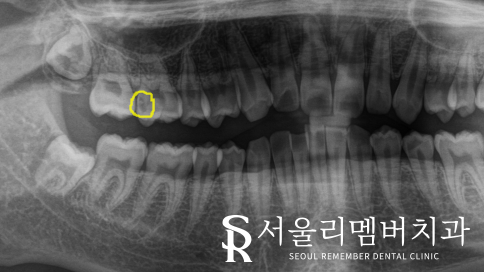

화면 기준 왼쪽이, 환자의 오른쪽입니다.

오른쪽 뒤에서 두 번째 어금니 교합면에

살짝 작은 검은 점이 있습니다.

사당동 치과 에서는 정확한 진단을 위해

전체적인 파노라마 사진을 찍어 확인해 보기로 했습니다.

전체적인 사진을 찍어보니

불투명한 빛이 비쳐 보이는 치아 안에

우식이 생긴 것을 확인할 수 있었습니다.

눈으로 봤을 때는 정확히 보이지 않았지만

사당동 치과 에서 사진을 찍어보니 확연히 관찰되네요.